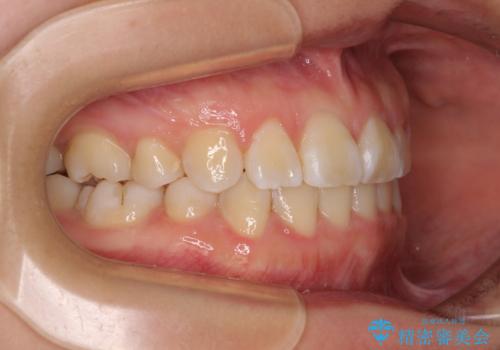

- 内側に生えている歯や埋もれた奥歯を気にして来院された患者様です。

顎の骨が小さいため、歯列が収まりきらずに叢生や未萌出となっている状態でした。

埋もれた奥歯を萌出させ、さらにデコボコを解消するために、上下左右の第1小臼歯4本に加え、親知らず4本も抜歯し、ワイヤー装置にて矯正治療を行うこととしました。